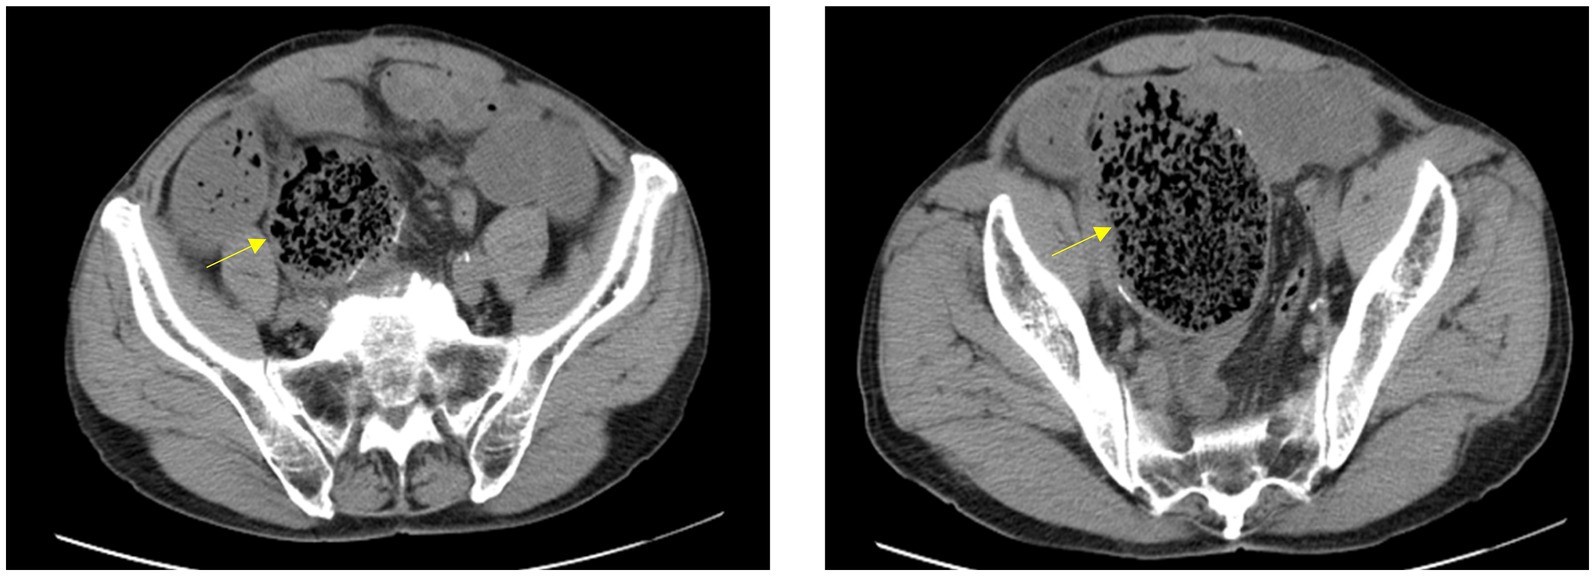

Physical examination revealed significant abdominal distension with a palpable mobile mass in the right lower quadrant. There was mild abdominal tenderness but no rebound. A mobile right lower quadrant mass was felt, and bowel sounds were markedly diminished. The patient underwent a comprehensive series of laboratory tests and diagnostic examinations upon hospital admission. The complete blood count revealed a neutrophil count of 7.21 × 10^9/L, with neutrophils accounting for 76.0% of white blood cells. The total white blood cell count was within the normal range. CT scan revealed a bag-like dilatation of the blind end of the original anastomosis, containing a fecal mass and causing intestinal obstruction with a proximal bowel dilatation (Figure 1).

Figure 1

CT scan reveals significant sac-like dilation of the original small intestinal anastomotic blind end, with fecal stagnation forming a mass inside. The proximal intestinal segment shows marked dilation.

Diagnosis relies on clinical suspicion, imaging (CT/MRI demonstrating blind loop dilatation ± fecal bezoar), and hydrogen breath testing for bacterial overgrowth (9). CT findings in this case revealed significant pouch-like dilation of the blind end at the original small bowel anastomosis, along with marked proximal intestinal dilation. Differential diagnoses include tumor or foreign body obstruction, necessitating a comprehensive evaluation. Treatment involves surgical resection of the blind loop (if feasible) and fecal bezoar removal, alongside antibiotics (e.g., rifaximin) for bacterial overgrowth (10). Endoscopic fragmentation may be attempted for small fecal bezoars, but laparotomy remains definitive for giant obstructions, as in our case (11). Long-term prevention includes dietary modifications (low-residue diets) and prokinetics for selected patients (12).